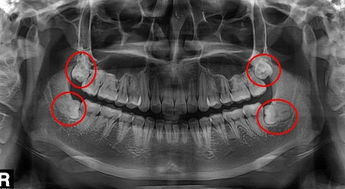

智齒位置圖片,紅圈內(nei) 的都是智齒

智齒是全口牙齒中萌出晚的,所以位置也在牙列末端接近喉嚨的位置,而且大部分由於(yu) 位置不夠,通常隻能萌出一部分,剩下的就埋在下麵的牙槽骨裏麵,或者是全部不萌出,上麵完全看不到,這種就是阻生的智齒,一般來說,智齒正常萌出的比較少。

不一定每個(ge) 人都有。一般來說,智齒的數量為(wei) 0-4顆,不一定每個(ge) 人都有4顆,上圖隻是僅(jin) 作為(wei) 參考,給出的4顆智齒都長全的圖片。

從(cong) 智齒常見的情況來看,目前這幾種智齒是比較多的(如上圖所示):

1、倒向鄰牙的智齒

2、倒向鄰牙相反方向一側(ce) 的智齒

3、垂直長的智齒

4、還有的智齒順著鄰牙橫著躺在牙槽骨裏麵

5、向著臉頰部生長的智齒

6、向著舌頭一側(ce) 生長的智齒

7、還有掉了個(ge) 頭,倒著長的智齒